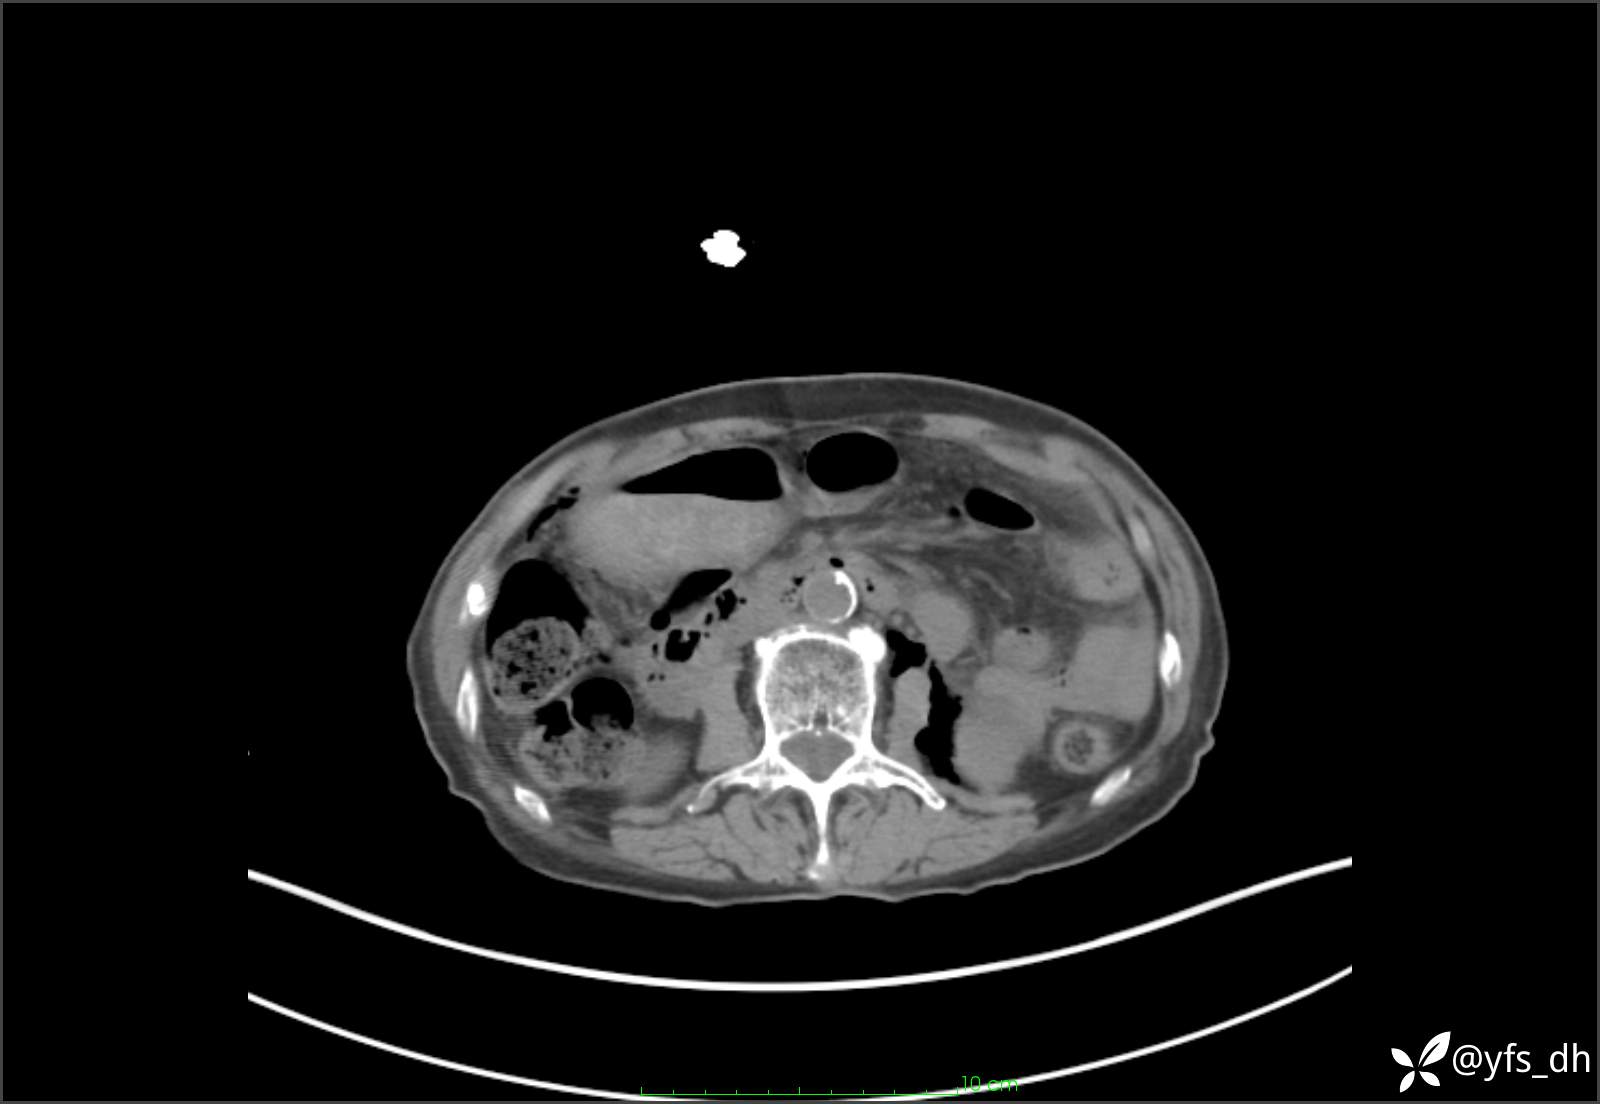

1.简要病史:患者4天前突发上腹部疼痛不适,但可以忍受。3小时前饭后突然加重,不能忍受后就诊。

2.简要手术记录:术中见腹盆腔大量肠液及粪便,乙状结肠中下段见一约3cm的破口。